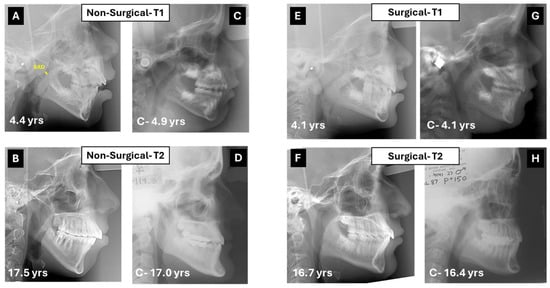

- Medical and surgical treatment can be beneficial, as both showed improvement in facial cephalometric features; however, surgery resulted in more improvement in mandibular shape and position. While the mandibular angle (Ar-Go-Me) closed in both treatment groups, the T2-T1 difference was statistically significantly greater in the surgical group (nearly 5°, Table 1). The closure indicates anterior rotation of the mandible and decrease in mandibular plane divergence. The consequent flattening of facial convexity (S-N-Me) was significantly greater in the surgical than the non-surgical group (T2-T1 difference = 4.4°, Table 1), further accentuating the efficacy of surgery (Figure 3).

- The patients who underwent surgery had more severe facial characteristics and were younger at pre-treatment (5.31 ± 1.99 years vs. 6.77 ± 2.84 years in surgical and non-surgical groups, Table 1). This initial condition may have been the reason for the otolaryngologist to perform and the parents to accept surgery. Treatment selection reflects the protocol followed by the treating otolaryngologist, technically indicating a selection bias, even if unavoidable in reference to the pertinent protocol. Consequently, the differences observed between groups may be attributed not only to the treatment modality but also to the initial severity of the condition, suggesting that severe obstructions are diagnosed early and are eligible for surgical treatment to reach the improvements observed in this study.